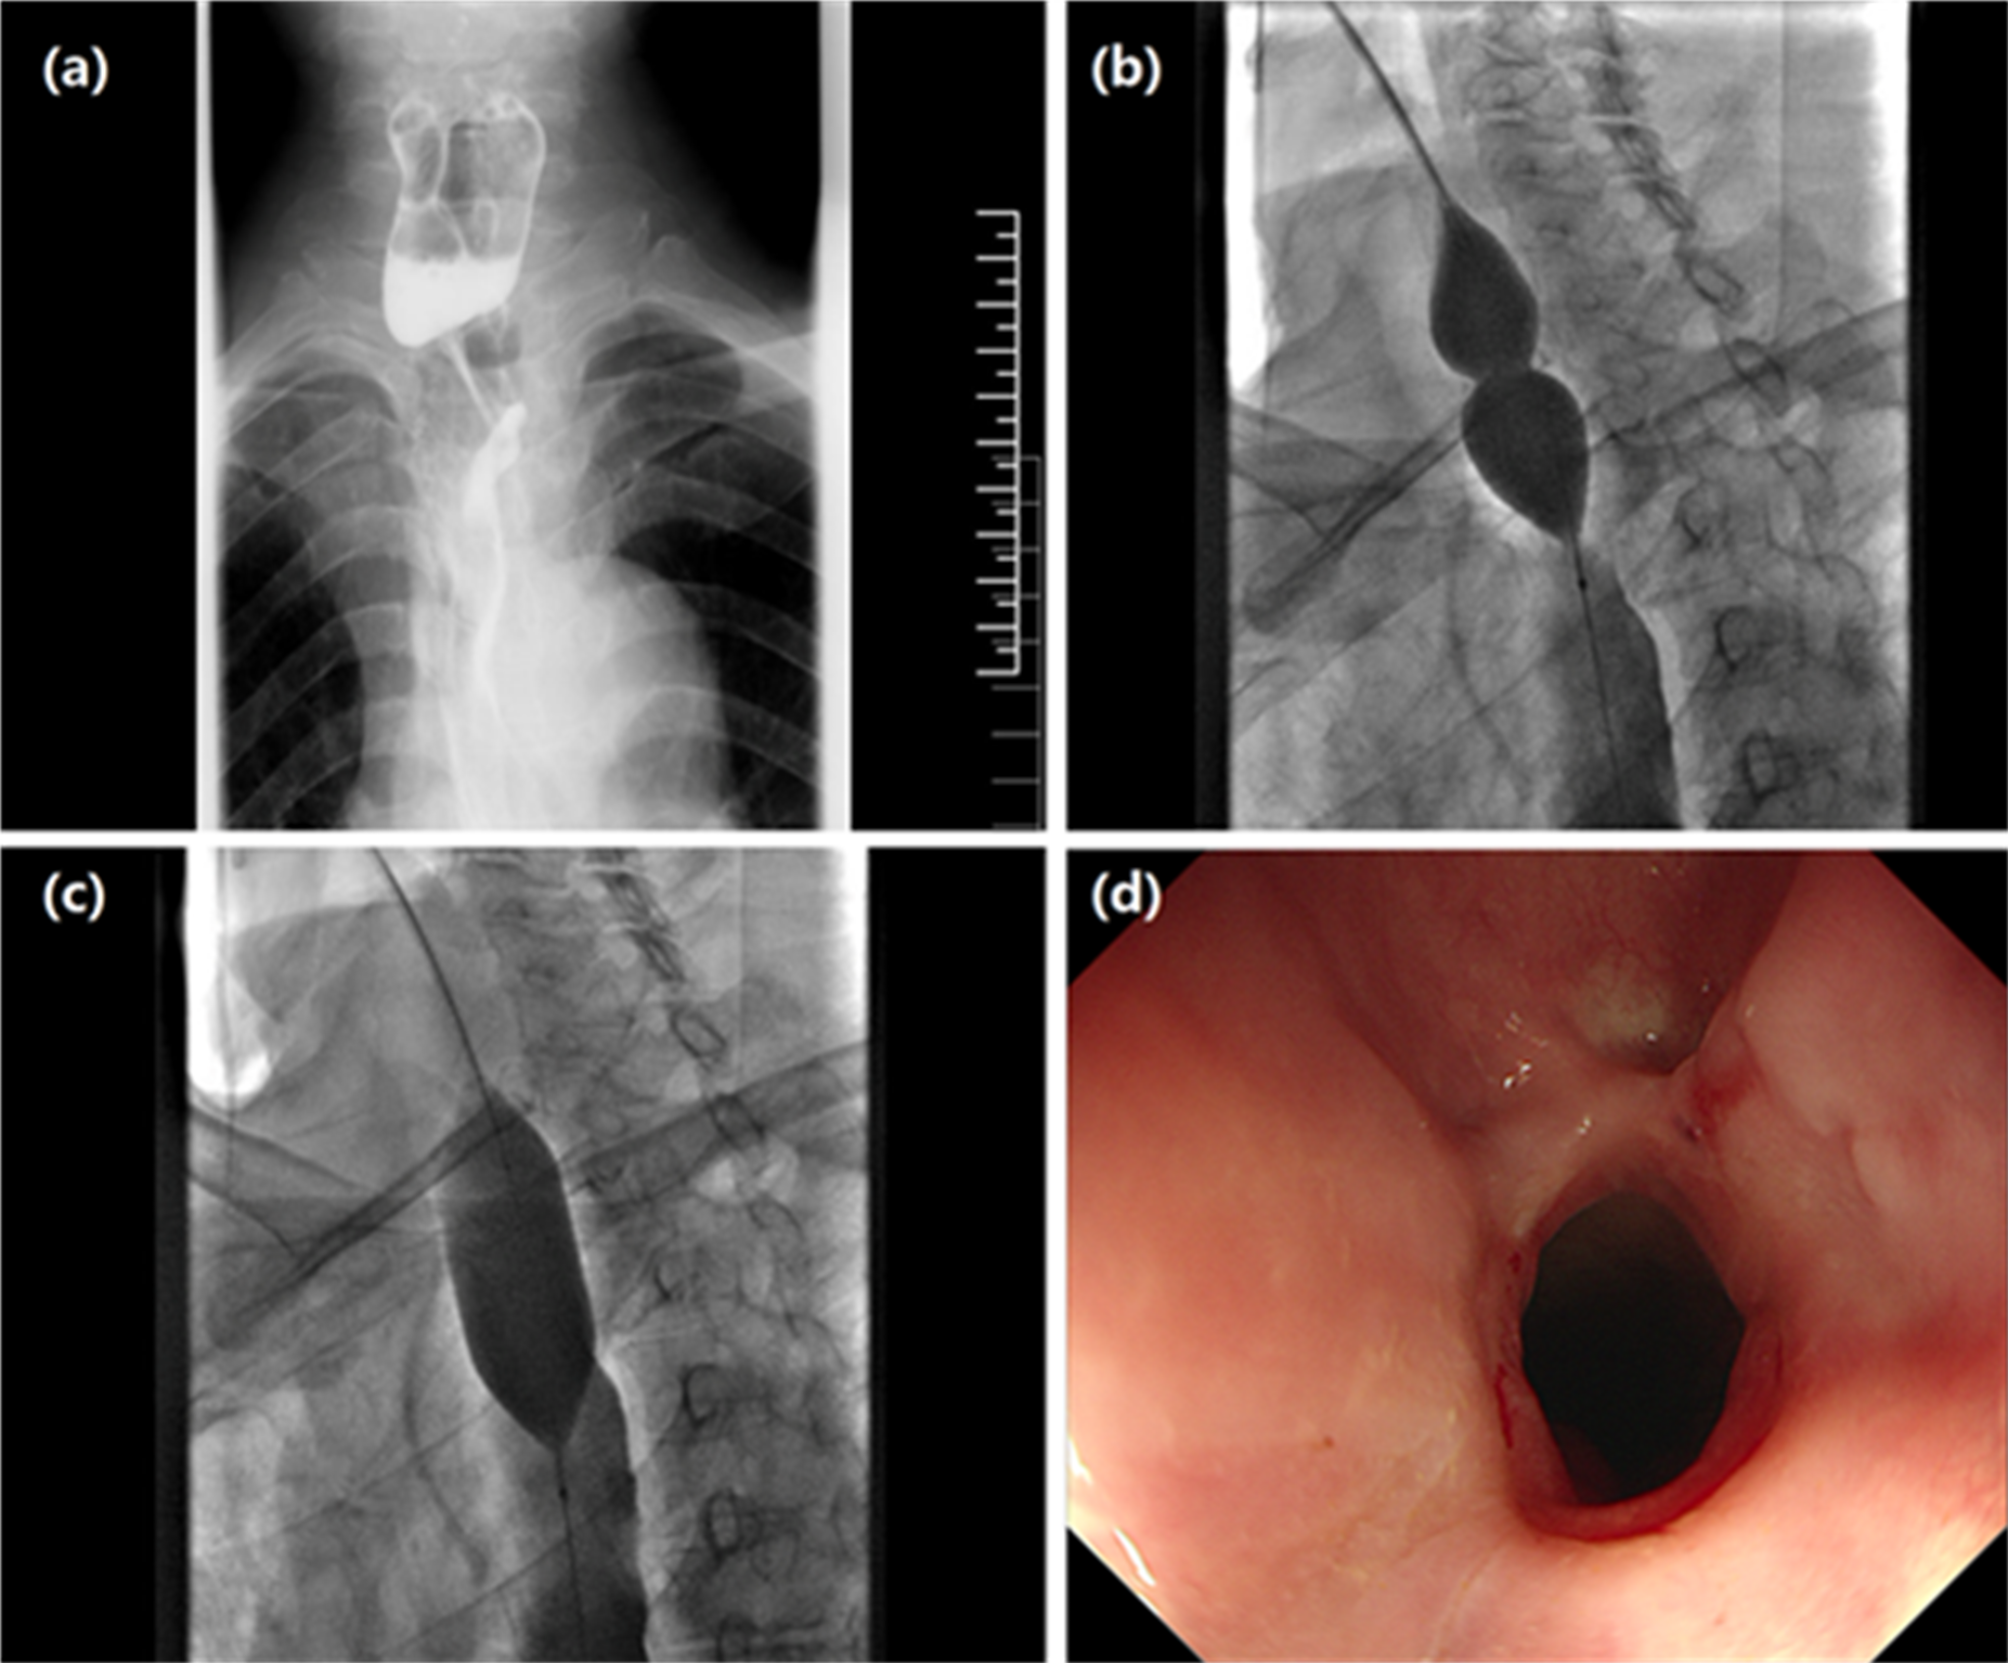

Fig. 2

A male patient underwent large balloon dilatation for anastomotic stricture. (a) An esophagogram showed severe stricture at the level of the sternoclevicular joint 2.8 months after esophagectomy for esophageal cancer. (b) Dilatation using Bard large balloon (26 mm in diameter, 40 mm in length) was done by positioning the balloon within the stricture. (c) The balloon catheter was dilated and inflated with 50% diluted contrast medium. (d) The esophagography showed a relief of esophageal stricture 10.1 months after dilatation, and the patient is able to eat normal diet during follow-up.